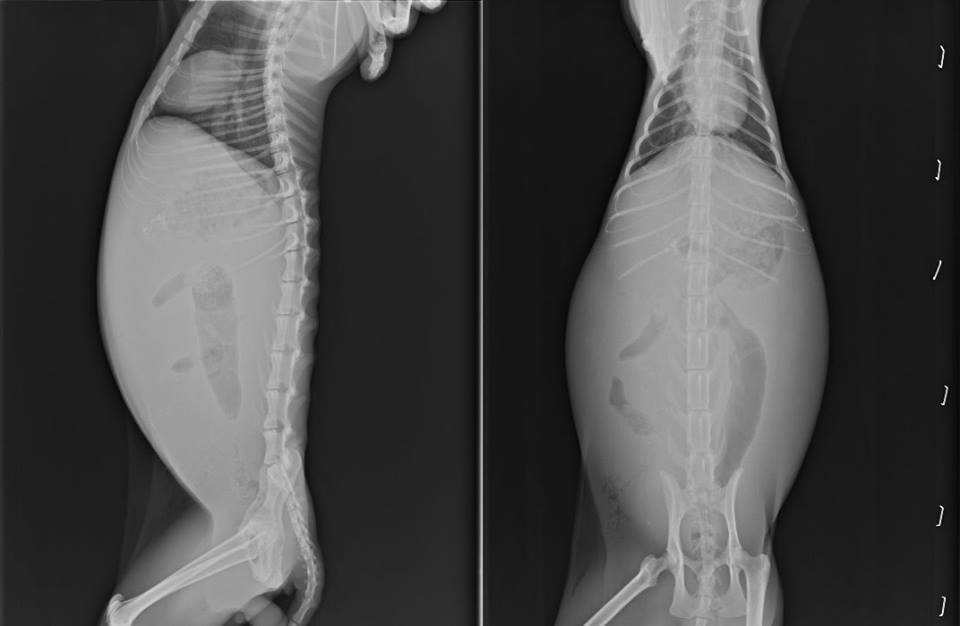

主題: 在路邊一直喘氣走不動貓咪 申請者姓名: 陳曉霏 花色: 申請日期: 2013-09-03 07:42:03 申請者部落格: 申請者臉書網址: https://www.facebook.com/xiaofeic 所在縣市/合作醫院: 台北市/極光動物醫院 治療費用: 12795元 需求人數: 14人 已結案 (2014-01-10 18:02:50) 報名人員: conbao wu、jojo、kelly(已付款)、劉詠欣、Hsin-Yi Chiao(已付款)、Tiffany Shen(已付款)、Grace Luo(已付款)、SASA(已付款)、超凡(已付款)、HI HI Little(已付款)、美石主義(已付款)、Chen Ping、波波(已付款)、ERic YU(已付款)、Huimin Liu(已付款)、Emily Chou(已付款)、Sharon Kuo x2(已付款)、 候補人員: 動物病情說明: 在路邊看見一隻貓咪一直在用力喘氣

經協會幫忙就醫後 確診為 腹膜炎

由於後期腹水已經越來越嚴重